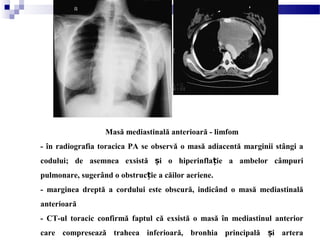

Masă mediastinală anterioară - limfom

- în radiografia toracica PA se observă o masă adiacentă marginii stângi a

codului; de asemnea exsistă i o hiperinfla ie a ambelor câmpuriș ț

pulmonare, sugerând o obstruc ie a căilor aeriene.ț

- marginea dreptă a cordului este obscură, indicând o masă mediastinală

anterioară

- CT-ul toracic confirmă faptul că exsistă o masă în mediastinul anterior

care compresează traheea inferioară, bronhia principală i arteraș